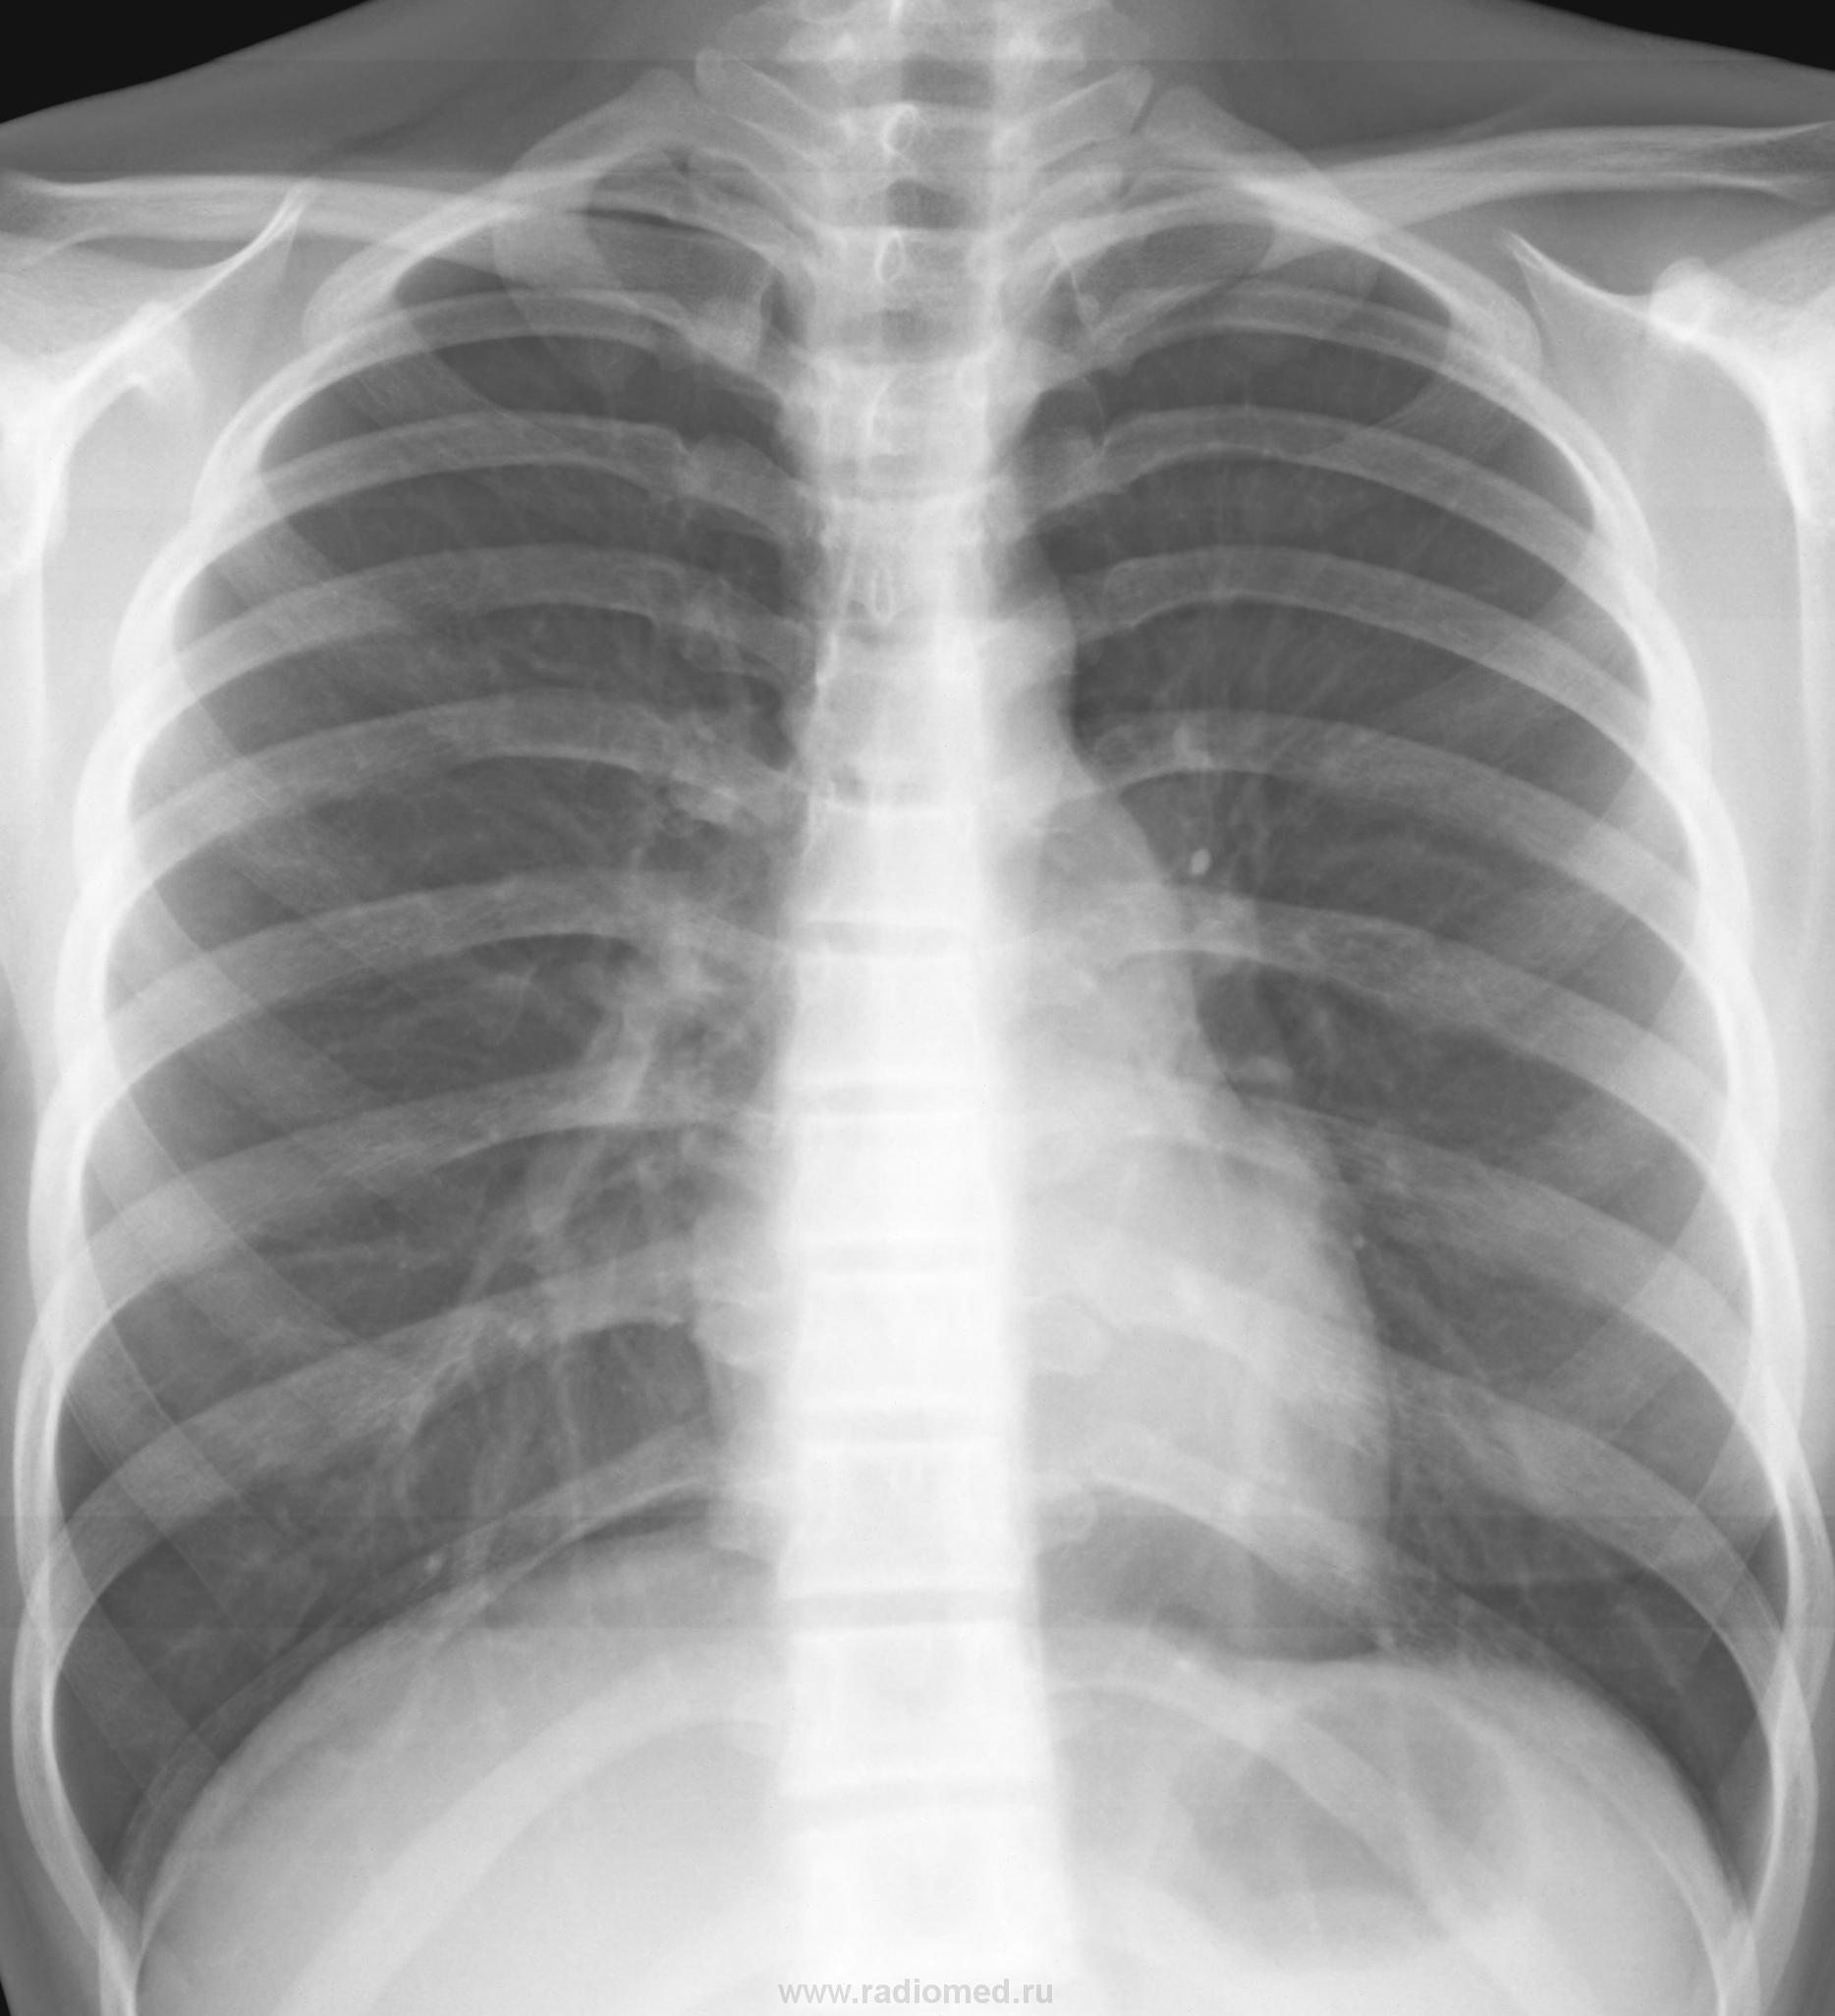

В глаза бросалась доп тень правее корня правого легкого.  После была правая боковая проекция (лаборант срезал верхушку - поэтому не буду его выкладывать с браком), на которой доп теней не наблюдал, во время выяснения анамнеза жизни девушки заметил что у нее длинные волосы в виде двух косичек с резинками на концах, пересняли в прямой проекции в моем присутствии как надо было - с убранными волосами. вот что получилось в итоге:

таким вот образом лаборанты подкидывают нам дополнительную работу, не соблюдая всех правилов укладки пациентов. Всем спасибо за участие в экспертизе.

Непонятна цель экспертизы, зачем раскрывать карты до завершения времени? В который раз убеждаюсь без бокового вообще не нужно оценивать патологию, хотя мысль о косе возникла сразу, но не думал что на экспертизу будет выставлен случай недоработки лаборанта.

лаборанту- выговор.

не сердитесь на меня коллеги - выставил потому что и такое в нашей работе встречается, хотелось бы знать можно ли заподозрить артефакт по первому снимку не увидя случайно длинных кос пациентки. а на боковых не всегда видно того что есть на самом деле, но боковой не стал выкладывать не по этой причине. лаборанту то выговор и показательный случай для начинающих. ведь анамнез и внимательность помогают избежать необоснованных допобследований.

Просто ни на что не похоже, да и анализу не поддавалось, интенсивность тени смущала, расположение. И основное просто от себя: не раз на сайте выставлялись случаи когда описывали разную патологию, а оказывались волосы + девушка. У самого есть грустный опыт когда думали о плохом, а оказалась просто раскошная коса.